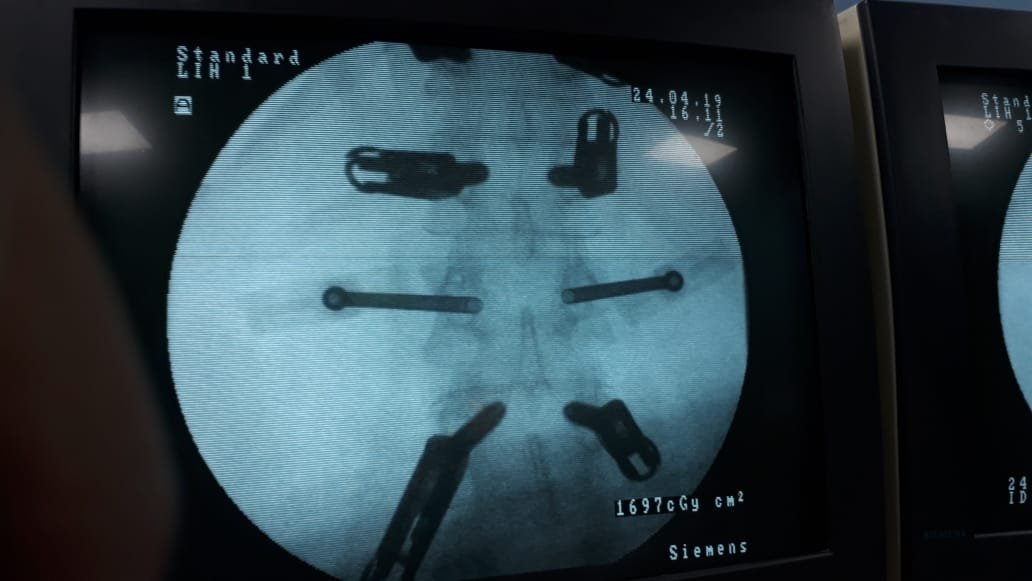

Posterior Instrumentation

Traumatic spinal injuries and spinal fusions are some spinal conditions that need instant posterior instrumentationHe places screws and MRI-compatible rods in the spine. This keeps the spine straight and stable. It prevents unwanted movement.